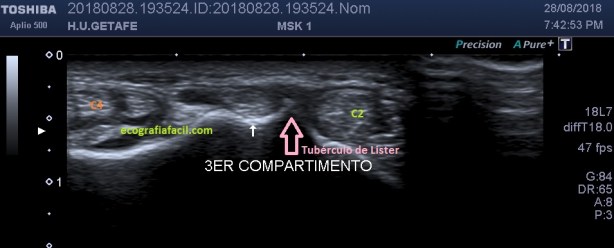

Criptorquidia: El testículo no descendido es una de las anomalías genitourinarias más comunes en niños. La mayoría de los testículos no descendidos son palpables y se localizan en el canal inguinal. Su aspecto ecogénico es normal, salvo si son vistos en la edad adulta, que pueden ser más pequeños y de ecogenicidad alterada. Objetivamente no van a estar en las bolsas y los vamos a encontrar donde marca el picto de la imagen 12. En ocasiones necesitan tratamiento quirúrgico. La flecha amarilla fina y alargada te marca la profundidad anómala debido a la piel y el tejido celular subcutáneo típico de la región inguinal, observa como cambia esta imagen respecto de cualquiera de las anteriores con los testes en sus bolsas.